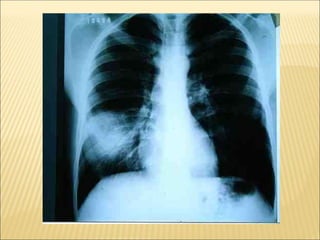

PADRÃO RADIOLÓGICO

• imagem de padrão alveolar do tipo consolidação com

broncograma aéreo, unilateral;

• imagens alveolares sem caracterização completa de consolidação;

• imagens intersticiais, reticulares ou reticulonodulares uni ou

bilaterais.

- RX SEMPRE ASSOCIADO COM QUADRO CLÍNICO.

- ajuda na definição da gravidade do quadro - envolvimento

multilobar e principalmente bilateral se associa à maior gravidade.

PADRÕES RADIOLÓGICOS PRINCIPAIS NAS

PNEUMONIAS

 Padrão intersticial: espessamento peribrônquico e infiltrado

intersticial difuso, hiperinsuflação, mais sugestivo de infecção viral

(ou asma).

 Padrão alveolar: condensações lobares ou segmentares,

especialmente quando associado a pneumatoceles, derrame ou

abscesso, sugere fortemente etiologia bacteriana.